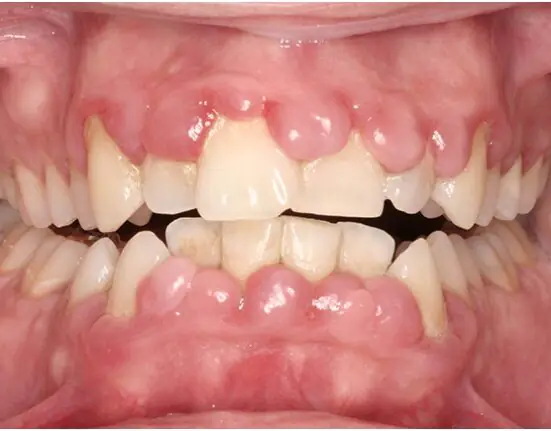

Not surprisingly, the patient’s inflammation was very severe, with heavy sublingual calculus. The patient also had extreme gingival hyperplasia, an overgrowth of gum tissue around the teeth that can have multiple causes, but is often a symptom of poor oral hygiene (Figure 1). During this first visit, the patient was examined by one of our dentists and x-rayed, and we determined we should begin treatment as soon as possible.